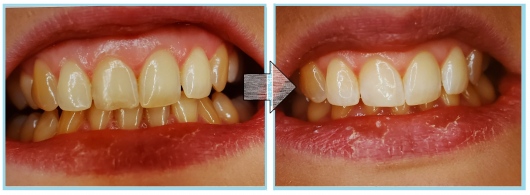

Jestem Amerykaninem, ale mieszkam w Polsce ponad 10 lat. Zajmuję się zachowawczą, leczeniem kanałowym pierwotnym i wtórnym pod mikroskopem, protetyką i prostą chirurgią. Wykonuję też Bonding i Flow Injection Technique.